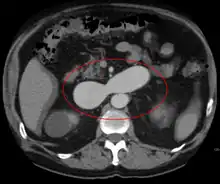

AVMs are diagnosed primarily by the following imaging methods:[12]

- Computed tomography (CT) scan is a noninvasive X-ray to view the anatomical structures within the brain to detect blood in or around the brain. A newer technology called CT angiography involves the injection of contrast into the blood stream to view the arteries of the brain. This type of test provides the best pictures of blood vessels through angiography and soft tissues through CT.

- Magnetic resonance imaging (MRI) scan is a noninvasive test, which uses a magnetic field and radio-frequency waves to give a detailed view of the soft tissues of the brain.

- Magnetic resonance angiography (MRA) – scans created using magnetic resonance imaging to specifically image the blood vessels and structures of the brain. A magnetic resonance angiogram can be an invasive procedure, involving the introduction of contrast dyes (e.g., gadolinium MR contrast agents) into the vasculature (circulatory system) of a patient using a catheter inserted into an artery and passed through the blood vessels to the brain. Once the catheter is in place, the contrast dye is injected into the bloodstream and the MR images are taken. Additionally or alternatively, flow-dependent or other contrast-free magnetic resonance imaging techniques can be used to determine the location and other properties of the vasculature.